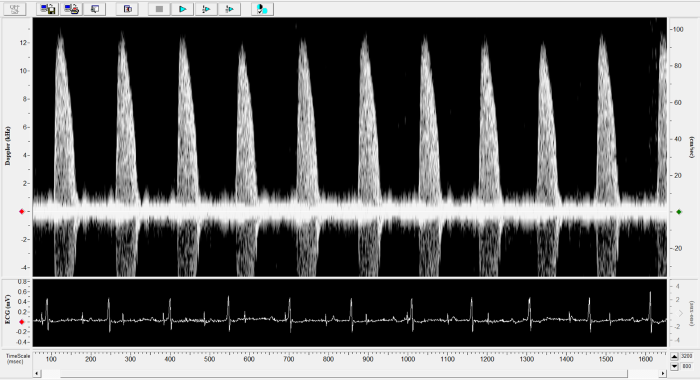

Imaging gallery - Doppler Flow Velocity System

Carotid Image. Image Credit: Scintica Instrumentation Inc.

Renal Flow. Image Credit: Scintica Instrumentation Inc.

Pulmonary Flow. Image Credit: Scintica Instrumentation Inc.

Mouse - Abdominal Aorta. Image Credit: Scintica Instrumentation Inc.

Mouse - TAC Procedure Imaging. Image Credit: Scintica Instrumentation Inc.

Mouse - Coronary Flow Reserve Imaging. Image Credit: Scintica Instrumentation Inc.

Rat - Left Carotid. Image Credit: Scintica Instrumentation Inc.

Rat - Transverse Aorta. Image Credit: Scintica Instrumentation Inc.

Rat - Right Carotid. Image Credit: Scintica Instrumentation Inc.

Rat - Abdominal Aorta. Image Credit: Scintica Instrumentation Inc.

Mouse - Left Anterior Descending Coronary Artery. Image Credit: Scintica Instrumentation Inc.

Mouse - Left Carotid. Image Credit: Scintica Instrumentation Inc.

Mouse - Mitral Inflow. Image Credit: Scintica Instrumentation Inc.

Mouse - Ascending Aorta. Image Credit: Scintica Instrumentation Inc.